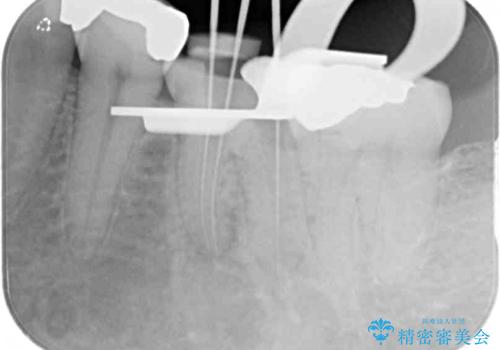

痛みが継続するため、「根管治療」と検索したところ、「ラバーダム」の重要性を知るところとなったようです。

根管治療を実施した後に、フルジルコニアクラウンにて補綴することとしました。

症状のあった歯に対しても根管治療を行い、同様に補綴治療を行いました。